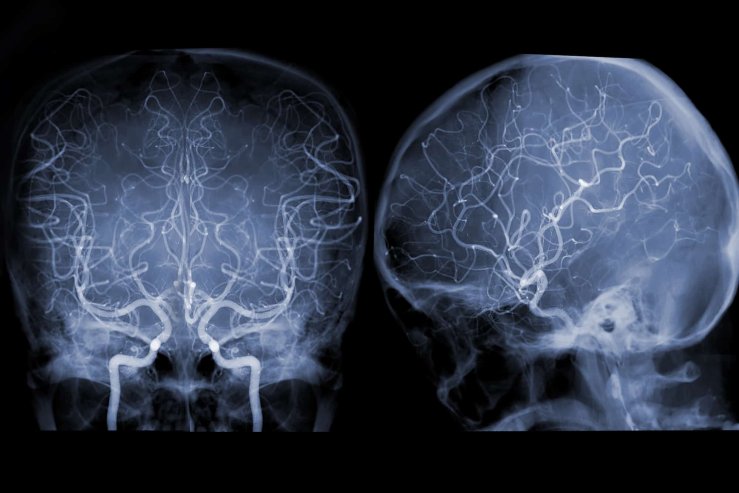

Відділення спеціалізується на діагностиці та лікуванні порушень мозкового кровообігу, аневризм, мальформацій, інсультів і невралгій судинного походження. Тут проводяться найскладніші мікрохірургічні та ендоваскулярні операції, які щодня рятують життя пацієнтів із критичними станами.

Для точної діагностики та контролю під час втручань використовуються:

- ангіографічний комплекс “Integris V 3000” (Нідерланди) — для детального дослідження судин голови та шиї;

- ультразвуковий апарат “Sonos 1000” — для оцінки кровотоку без інвазивного втручання;

- операційний мікроскоп “OPMI Vario” (Carl Zeiss, Німеччина) — для високоточної мікрохірургії.

Таке оснащення дозволяє лікарям не лише швидко встановити діагноз, а й одразу обрати оптимальну тактику лікування.

Основні напрями роботи включають:

- Ішемічні ураження мозку — ендартеректомії, шунтування, ангіопластика та стентування артерій, що відновлюють кровопостачання і запобігають інсультам;

- Артеріальні аневризми та мальформації — кліпування, ендоваскулярне виключення аневризм, видалення мальформацій для запобігання розриву судин;

- Геморагічні інсульти — видалення гематом і шунтуючі операції з використанням КТ-навігації. Летальність у відділенні — лише 23,8%, один із найнижчих показників в Україні при такій складності випадків;

- Невралгія трійчастого нерва — мікрохірургічна операція Джанета, що усуває судинну компресію і повертає пацієнтові життя без болю.

Поєднання високотехнологічної діагностики, досвідчених нейрохірургів і міждисциплінарного підходу (співпраця з кардіохірургами, анестезіологами, неврологами) дозволяє виконувати навіть симультанні операції — одночасно на серці та судинах мозку. Це унікальний рівень допомоги, який доступний лише у великих нейрохірургічних центрах.